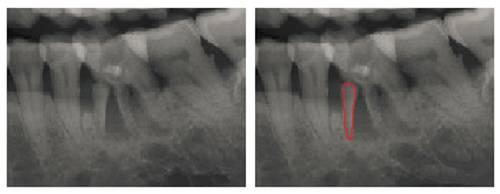

拍X光片后才能发现牙根已经劈裂

无法治疗了~